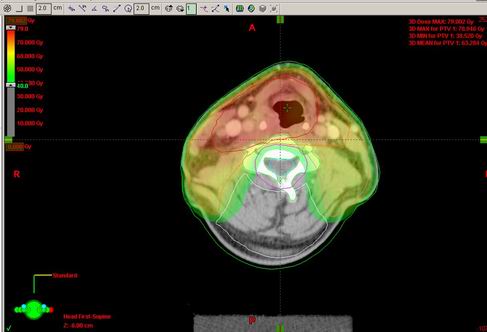

53-letý Z.T.

Karcinom hypofaryngu, recesus piriformis l.dx T2 N2b M0, spinoca

Kurativní RT – konvenční frakcionace

Zakreslení struktur:

DVH:

Dávka > 40Gy:

Dávka > 45 Gy:

Dávka > 54 Gy:

Dávka > 60 Gy:

Dávka > 72 Gy: